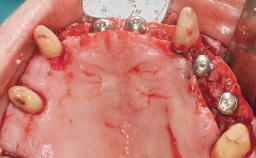

A 63-year-old male patient was referred for a consultation and treatment of partial edentulism in the maxilla. The patient presented with residual anterior teeth and declined a partial removable prosthesis. He reported that the maxillary posterior teeth had been extracted due to mobility and periodontal disease two months before the consultation. The patient’s chief complaint was that his residual maxillary teeth were mobile and that he was unable to chew. The patient’s desire was a stable and comfortable fixed maxillary rehabilitation. The patient was a light smoker (fewer than 10 cigarettes/ day), and his medical history was without significant findings. He was not on any regular medication at the time of consultation. The extraoral examination revealed a normal physiognomy with a correct distribution of the facial thirds. The patient presented a low lip line, and the transition line between teeth and soft tissues was not exposed during a forced smile.

Defining Characteristics Fully edentulous upper jaw to be rehabilitated with four or more implants

Modality 6+ implants with immediate loading